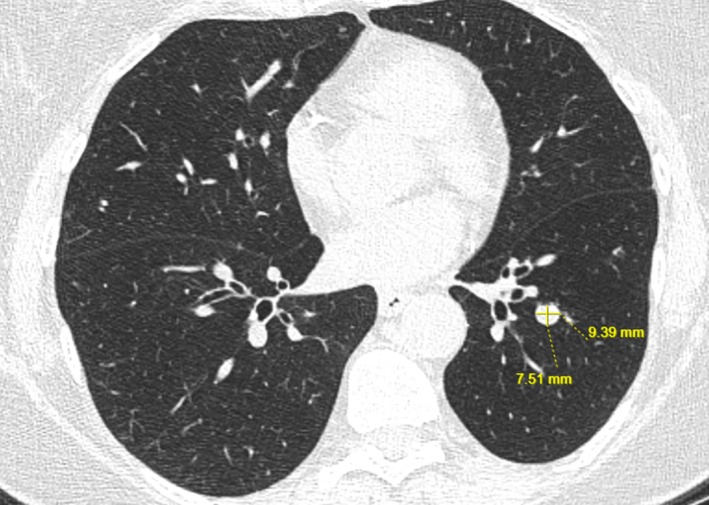

Therapeutic treatment of lung nodules by ablation is a new field. Even though not considered standard of care, lung nodule ablation can be appropriate for select cases. Even though ablation is a safe and well-tolerated procedure, bleeding is a potential complication. We introduce our stepwise approach through two cases on how we AIM (Anticipate/Adjust, Image, Manage) to prevent uncontrolled bleeding during Robotically Assisted Bronchoscopic Ablation: 1. Anticipate structures with high risk for bleeding and adjust accordingly, accounting for the needle ablation field; 2. Image: utilise cone beam CT before the first and after each ablation session to screen for bleeding; 3. Manage bleeding by pre-emptively utilising Fogarty balloon occlusion.